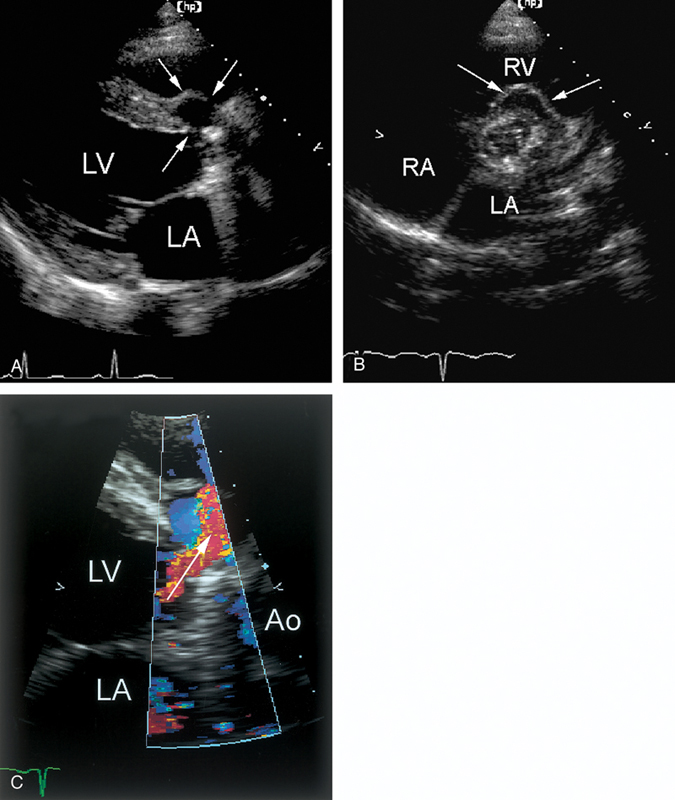

فحوصات تشخيصية لبعض امراض القلب والشرايين التاجية